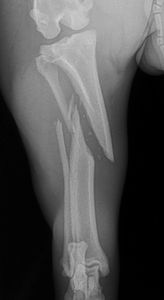

This patient was a small cat who received an unknown type of trauma to her hindlimb, causing a severe fracture of her left femur. There were multiple fragments, and the site was unstable. Unfortunately, a cast/splint, or a simple pin would not be sufficient to stabilize the fracture site and allow the bone to heal.

During surgery, the bony fragments were reduced, and secured in place with a pin and circlage wire. Then a 1.5mm low contact dynamic compression plate (LCDCP) was placed in a buttress fashion to reduce the fracture and provide stability. After a few days this lucky kitty was walking almost normally, and after 4-6 week of healing no lameness or clinical symptoms were noticed at all.